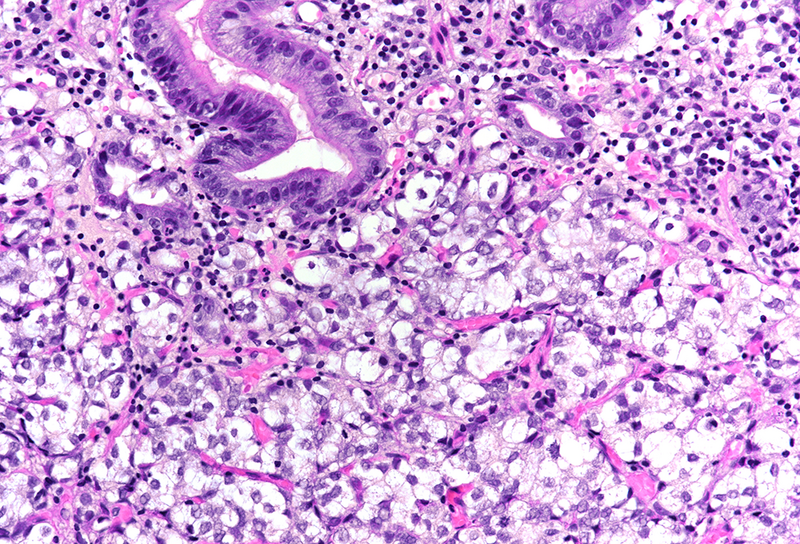

On low power, nodular infiltration of the corpus mucosa by middle-size pale to basophilic tumour cells is seen, arranged in solid nest-like arrangement lacking glandular appearance (Panel C-D). The surface epithelium is not involved, there is no background inflammation, atrophy and/or metaplasia. The tumour cells are positive for pan-keratin, keratin 8/18, however negative for keratins 7 and 20. This peculiar keratin profile prompted staining for Prostate-specific membrane antigen (PSMA, Panel E) and NKX3-1 which is an androgen-regulated, prostate-specific homeobox gene (Panel F). Ultimately, diagnosis of prostate cancer metastatic to the stomach was made.